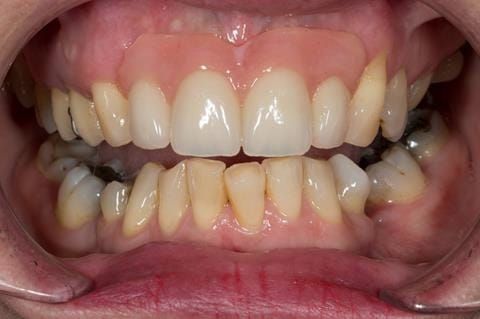

Provision of a maxillary cobalt chromium based partial denture/protective occlusal splint in a heavily restored dentition

- High smile line showing gum above gingival zeniths of upper front teeth when smiling. Aesthetic failure of the upper four incisors with inflammation of the gingivae and mis-match of the gingival zenith levels.

- Other than the maxillary incisors the remaining dentition was in marginally better condition being moderately to heavily restored. Many will probably require replacement and restoration from time to time mainly from wear and tear owing to occlusal forces.

Following consultation and second discussion appointment the patient chose to have option 3 namely, a maxillary cobalt chromium based partial denture/protective occlusal splint. The clinical situation and treatment process is shown in detail below with photographs. The patient was successfully rehabilitated with this and her quality of life considerably improved. The clinical work was provided by Finlay and the technical work by Rowan.